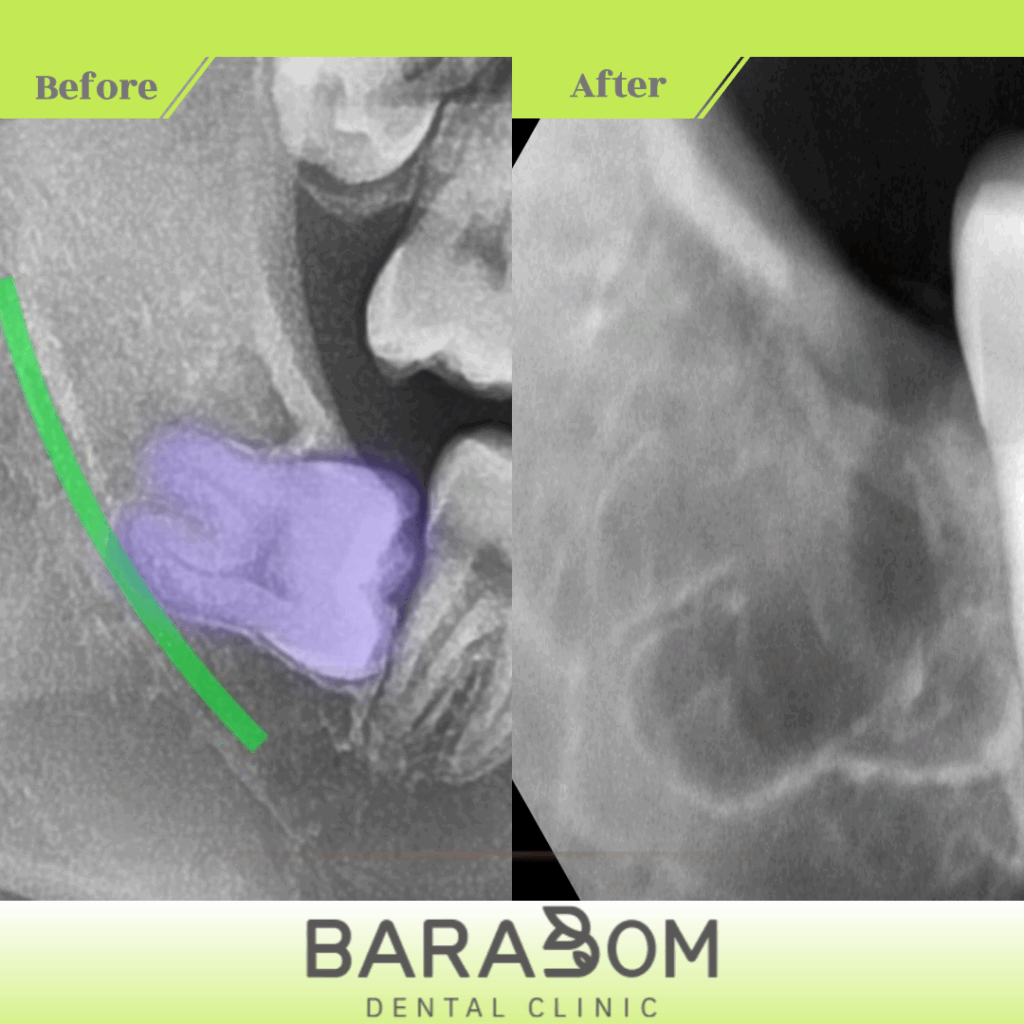

4. 발치 후 확인 과정

치아를 분할하여 제거한 후에는

치근이 남아있지 않은지

방사선 사진(PA)으로 확인합니다.

잔존 치근이 있으면

염증의 원인이 될 수 있기 때문이죠.

확인 후 지혈제를 넣고

봉합하여 발치 부위를 마무리합니다.